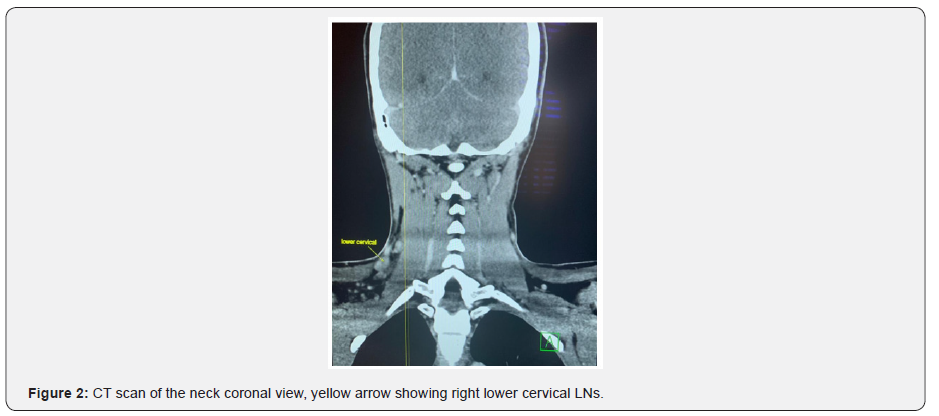

A pan CT was done, revealed multiple enlarged right upper and lower deep cervical lymph nodes in the neck, they are well defined, and homogenous, the largest measures about 19x11mm, few other small left upper and lower deep cervical and bilateral supraclavicular lymph nodes noted. The largest one measures about 10x6mm, also showed normal CT features of the nasopharynx, oropharynx, larynx, supraglottis, hypopharynx, vocal cords, pterygo-palatine, and pterygo-maxillary fossae, parapharyngeal and retropharyngeal spaces, parotid and submandibular glands, the rest of the paranasal sinuses were unremarkable.

CT chest showed, few small tissue nodules noted at the lateral segment of the right lower lobe and lateral segment of middle lobe of the lung, the largest one measures about 2x2mm, with no dense calcifications inside. Other CT findings showed bilateral axillary lymph nodes, the largest measures about 10x9mm. The course and caliber of the trachea and esophagus were normal, with no mediastinal and hilar lymphadenopathy. CT abdomen and pelvis showed right inguinal lymph nodes, the largest one about 11x7mm. During his hospital stay, a multiple disciplinary team was engaged including the oncology. And with proper counseling of the patient, the decision was to go for right hemithyroidectomy and lymph node excisional biopsy. Patient underwent the surgery and was in good post-operative condition with no intra or post-operative complications. Samples sent for histopathology and came as multifocal papillary microcarcinoma of the thyroid and Hodgkin lymphoma (nodular sclerosis) from the enlarged lymph nodes (Figures 1-10).